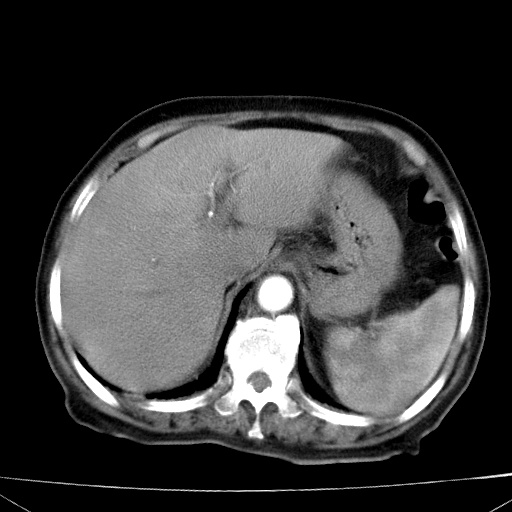

网站人气太旺!昨天的帖子就沉到海底,只好再发贴!ct18338:女 78岁,肝胆病变,已增强,再会诊!原帖链接:http://www.radida.com/bbs/forum.php?mod=viewthread&tid=50032

1)考虑胆囊癌侵犯肝脏并肝门区、腹膜后及右侧膈角后淋巴结转移。2)肝左叶近肝顶部囊肿。3)肝左叶肝内胆管结石。4)左肾近下极囊肿。